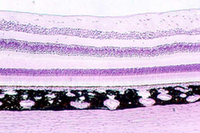

- Eye